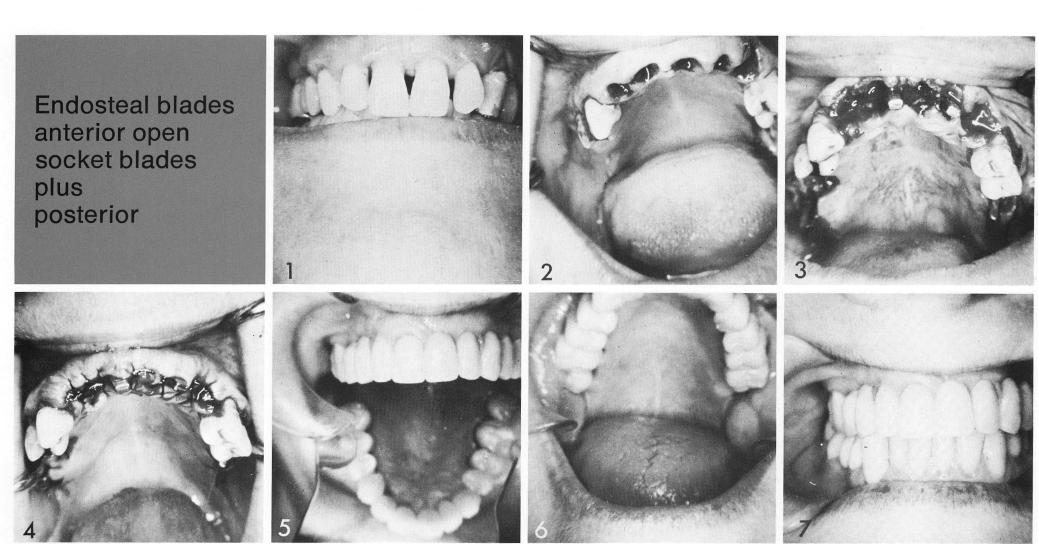

Endosteal blade

anterior open socket blades

plus

posterior

Here the anterior teeth were so loose (1) that they were extracted by hand. Very little damage was done to the residual ridge during tooth extraction (2). An open-socket bladevent was used anteriorly (3), crossing the mid-line to anchor the shoulder in the bone between the two former central incisors. Posteriorly other bladevents were inserted (4), and the restoration eventually seated (5,6). As with all cases, the occlusion is carefully checked and balanced.

1 Loose maxillary anterior teeth

2 An open socket maxillary bladevent implant used anteriorly